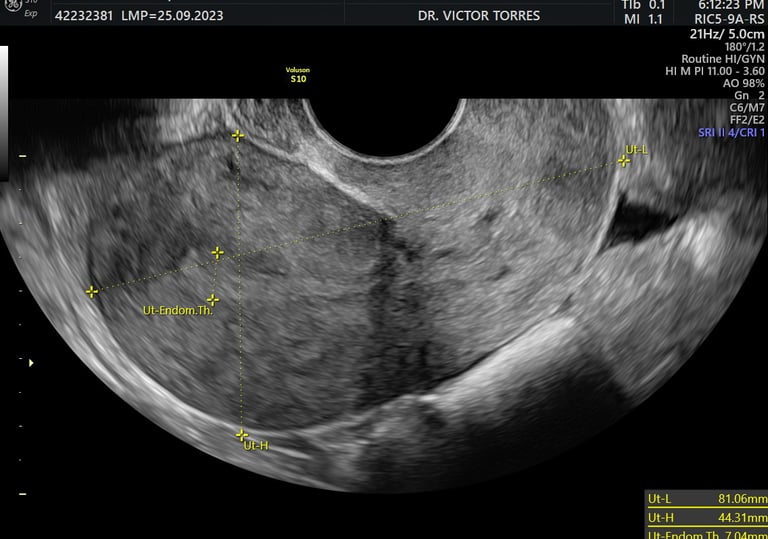

cervicometría